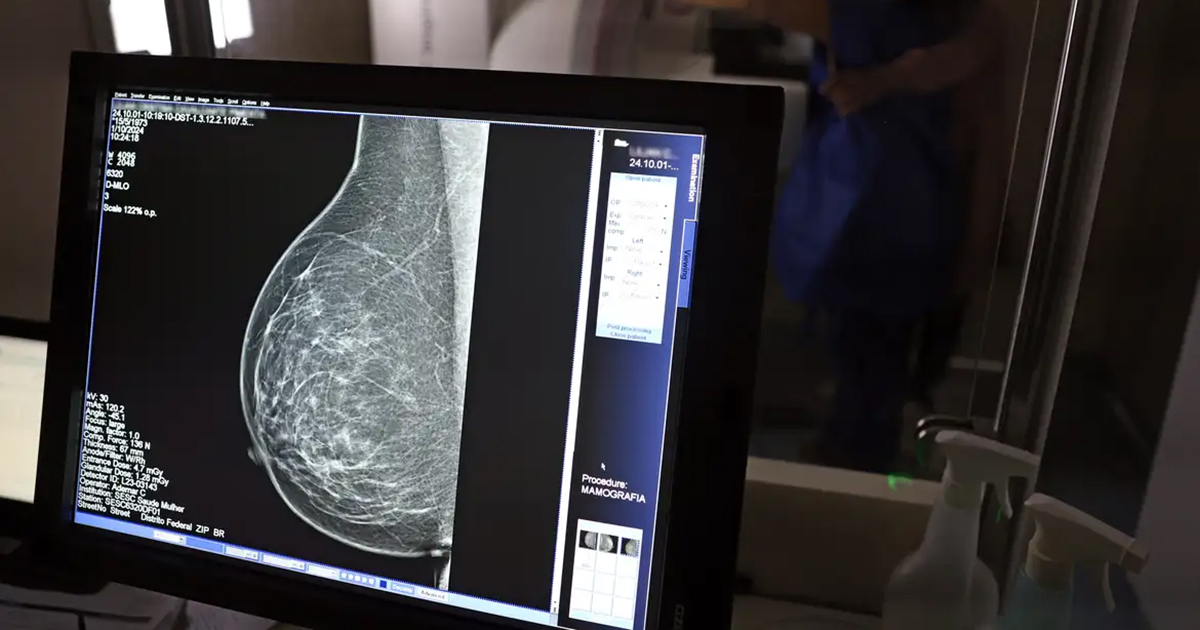

Foi publicada no Diário Oficial da União, uma Lei que fortalece o acesso das mulheres ao exame de mamografia fornecido pelo Sistema Único de Saúde (SUS). A partir de agora, o procedimento é garantido a mulheres a partir dos 40 anos de idade. Anteriormente, a idade em que o atendimento era oferecido, salvo casos especiais, era 50 anos.

Assinada pelo presidente Luiz Inácio Lula da Silva (PT) e pelos ministros Alexandre Padilha (Saúde), Macaé Evaristo (Direitos Humanos e da Cidadania) e Márcia Lopes (Mulheres), a nova lei altera a Lei nº 11.664, de 29 de abril de 2008, que dispõe sobre a efetivação de ações de saúde que assegurem a prevenção, a detecção, o tratamento e o seguimento dos cânceres do colo uterino, de mama e colorretal no âmbito SUS. Agora, o texto determina que o exame de mamografia será garantido a todas as mulheres a partir dos 40 anos, conforme diretrizes do Ministério da Saúde, que poderão estender o procedimento a outras faixas etárias.

A garantia ao exame se dará mesmo que as mulheres não apresentem sinais ou sintomas de câncer. A faixa etária dos 40 aos 49 anos concentra 23% dos casos da doença e a detecção precoce aumenta as chances de cura.

A recomendação para as mulheres a partir dos 40 anos é que o exame de mamografia seja feito sob demanda, em decisão com o profissional de saúde. A paciente deve ser orientada sobre os benefícios e desvantagens de fazer o rastreamento.

Mulheres nesta idade tinham dificuldade com o exame na rede pública de saúde em função da avaliação de histórico familiar ou necessidade de já apresentar sintomas. Apesar disso, as mamografias no SUS em pacientes com menos de 50 anos representam 30% do total, equivalente a mais de 1 milhão em 2024.